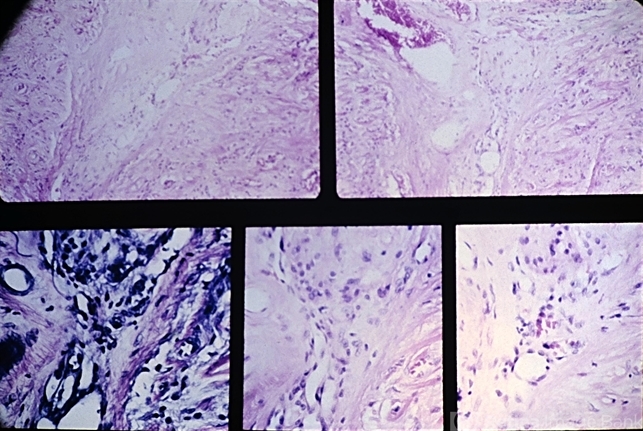

- central retinal vein occlusion (CRVO), lamina cribrosa, endothelial

- Central retinal vein occlusion. There is a recanalized thrombus in the central retinal vein at the level of the posterior aspect of the lamina cribrosa. Prominent endothelial cell proliferation is present at the proximal area of the thrombus.